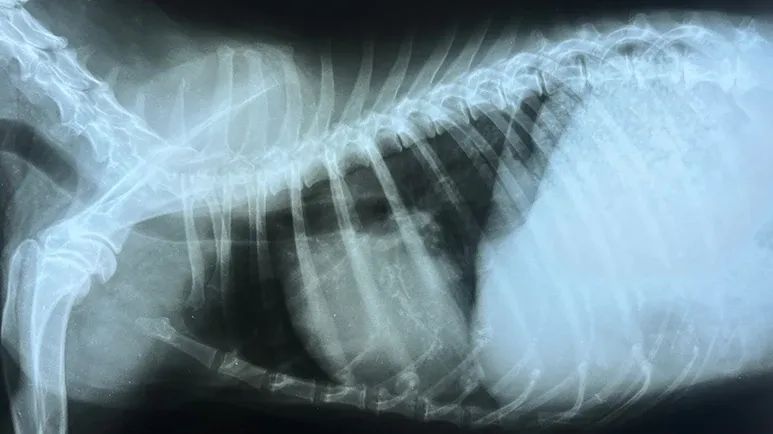

X-rays of your dog’s chest will help your vet determine if there’s evidence of heart failure, and an echocardiogram may be ordered to check for visible changes in the heart valves or chambers.